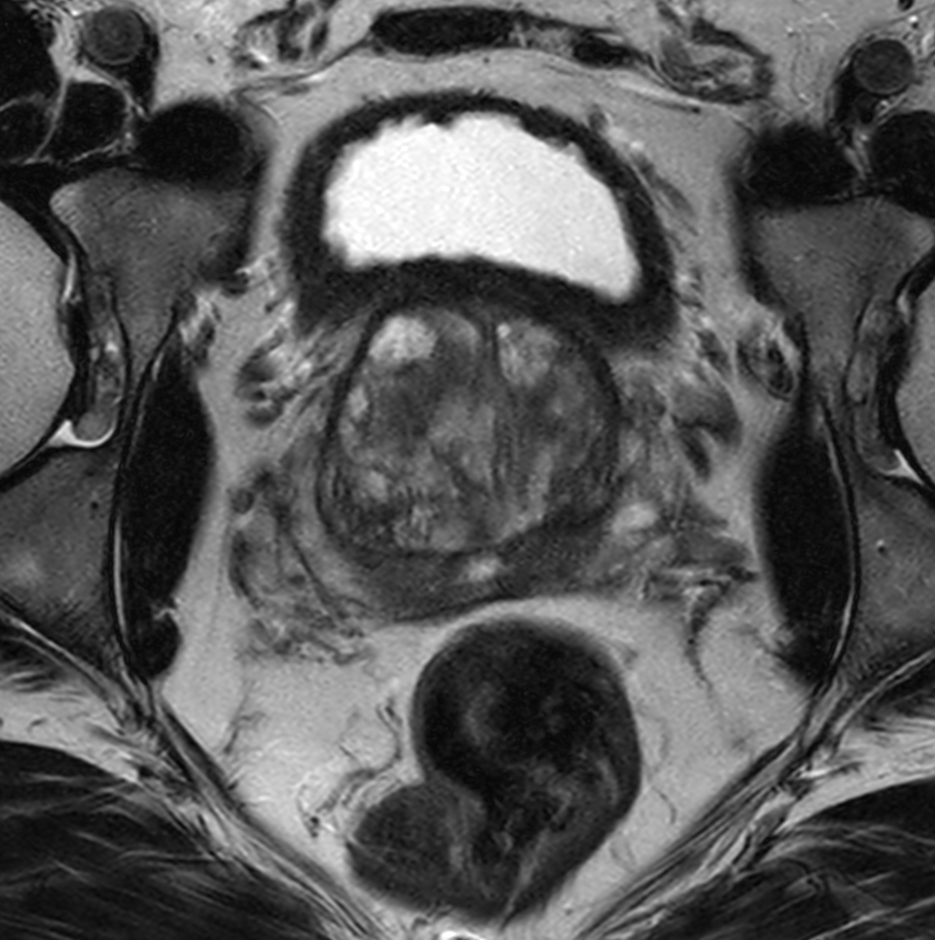

Axial T2w TSE